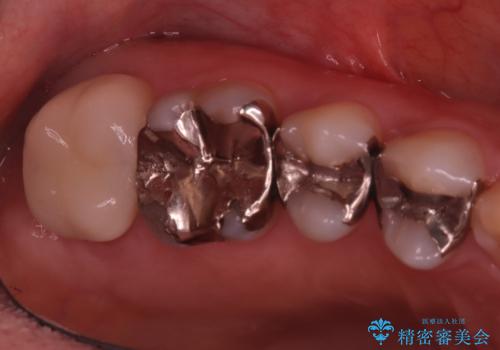

- 主訴:右下のセラミックのブリッジが何度も同じところで折れて壊れてしまう。

対合歯との咬合関係において、右下7番目と6番目の被せものの連結部がたわみやすい環境にあったため、ブリッジの新製ではなくインプラント治療を行いすべての歯を単冠仕上げとすることにしました。

何度も右下6、7間でブリッジが折れてしまうとのことでした。対合歯とブリッジの連結部が強く当たりたわみやすい状態でした。破折しずらい金属を使用したブリッジの選択もありましたが、支台歯(右下7)が失活歯場合、破折リスクが高く、破折してしまった場合にまたブリッジを外しての再治療になってしまう可能性を説明したところ、全て単冠仕上げとできるインプラント治療を希望されました。

右下5番のクラウンは、ブリッジを切断しそのまま使用していただいています。